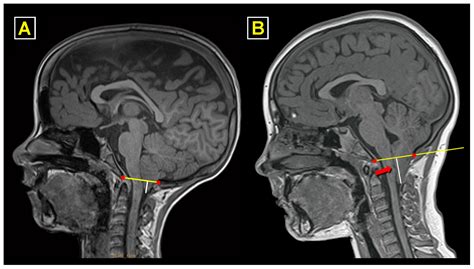

• Imaging Studies: X-rays, MRI, or CT scans may be ordered to visualize the joint and confirm the diagnosis.